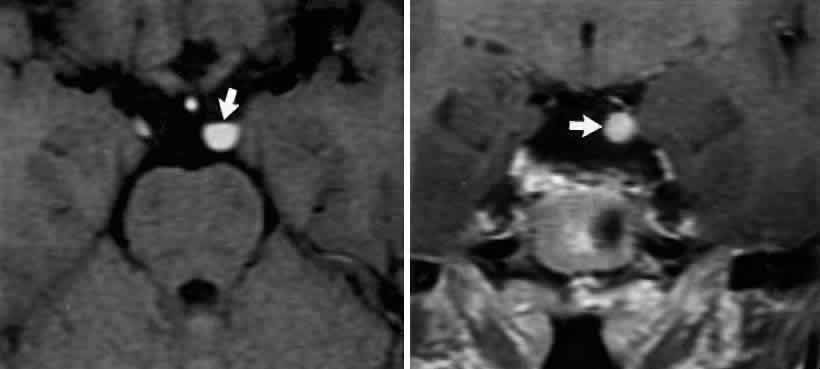

Primary neurinoma of the oculomotor nerve is a relatively rare lesion that should be considered in children or young adults with insidious third nerve palsy. These may occur in the cavernous or interpeduncular portion of the nerve (Fig. 13).99,100

Fig. 13. Insidiously progressive third nerve palsy due to oculomotor neurinoma (arrows) in 16-year-old girl. MRI T-1, enhanced axial (top) and coronal (bottom) sections.